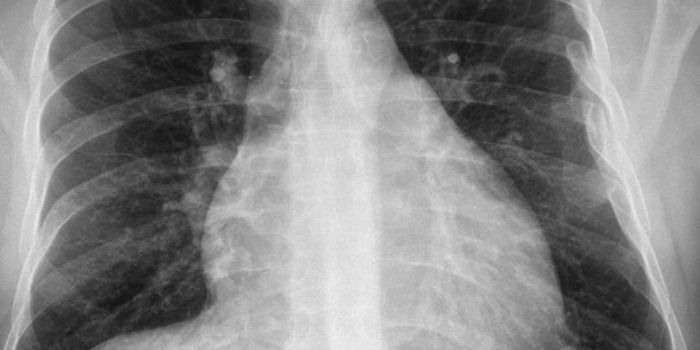

Cardiology is an ever-evolving branch of medicine concerned with disease and disorders of the heart. Cardiology trending provides articles and resources to keep you informed on risk factors, causes and prevention of heart disease, evidence-based research and advances in treatment.